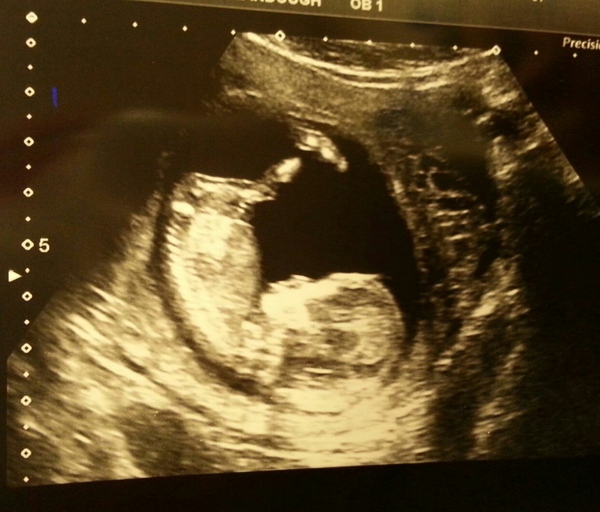

Had my 12 week scan yesterday. .baby all happy..doing a yoga pose!..v relieved...just the downs blood to come back now then I'm going to relax proper into this pregnancy malarki.

Awwwww Trinity such a clear photo! Congratulations! Flowers

Congratulations Trinity, that's an amazing picture!